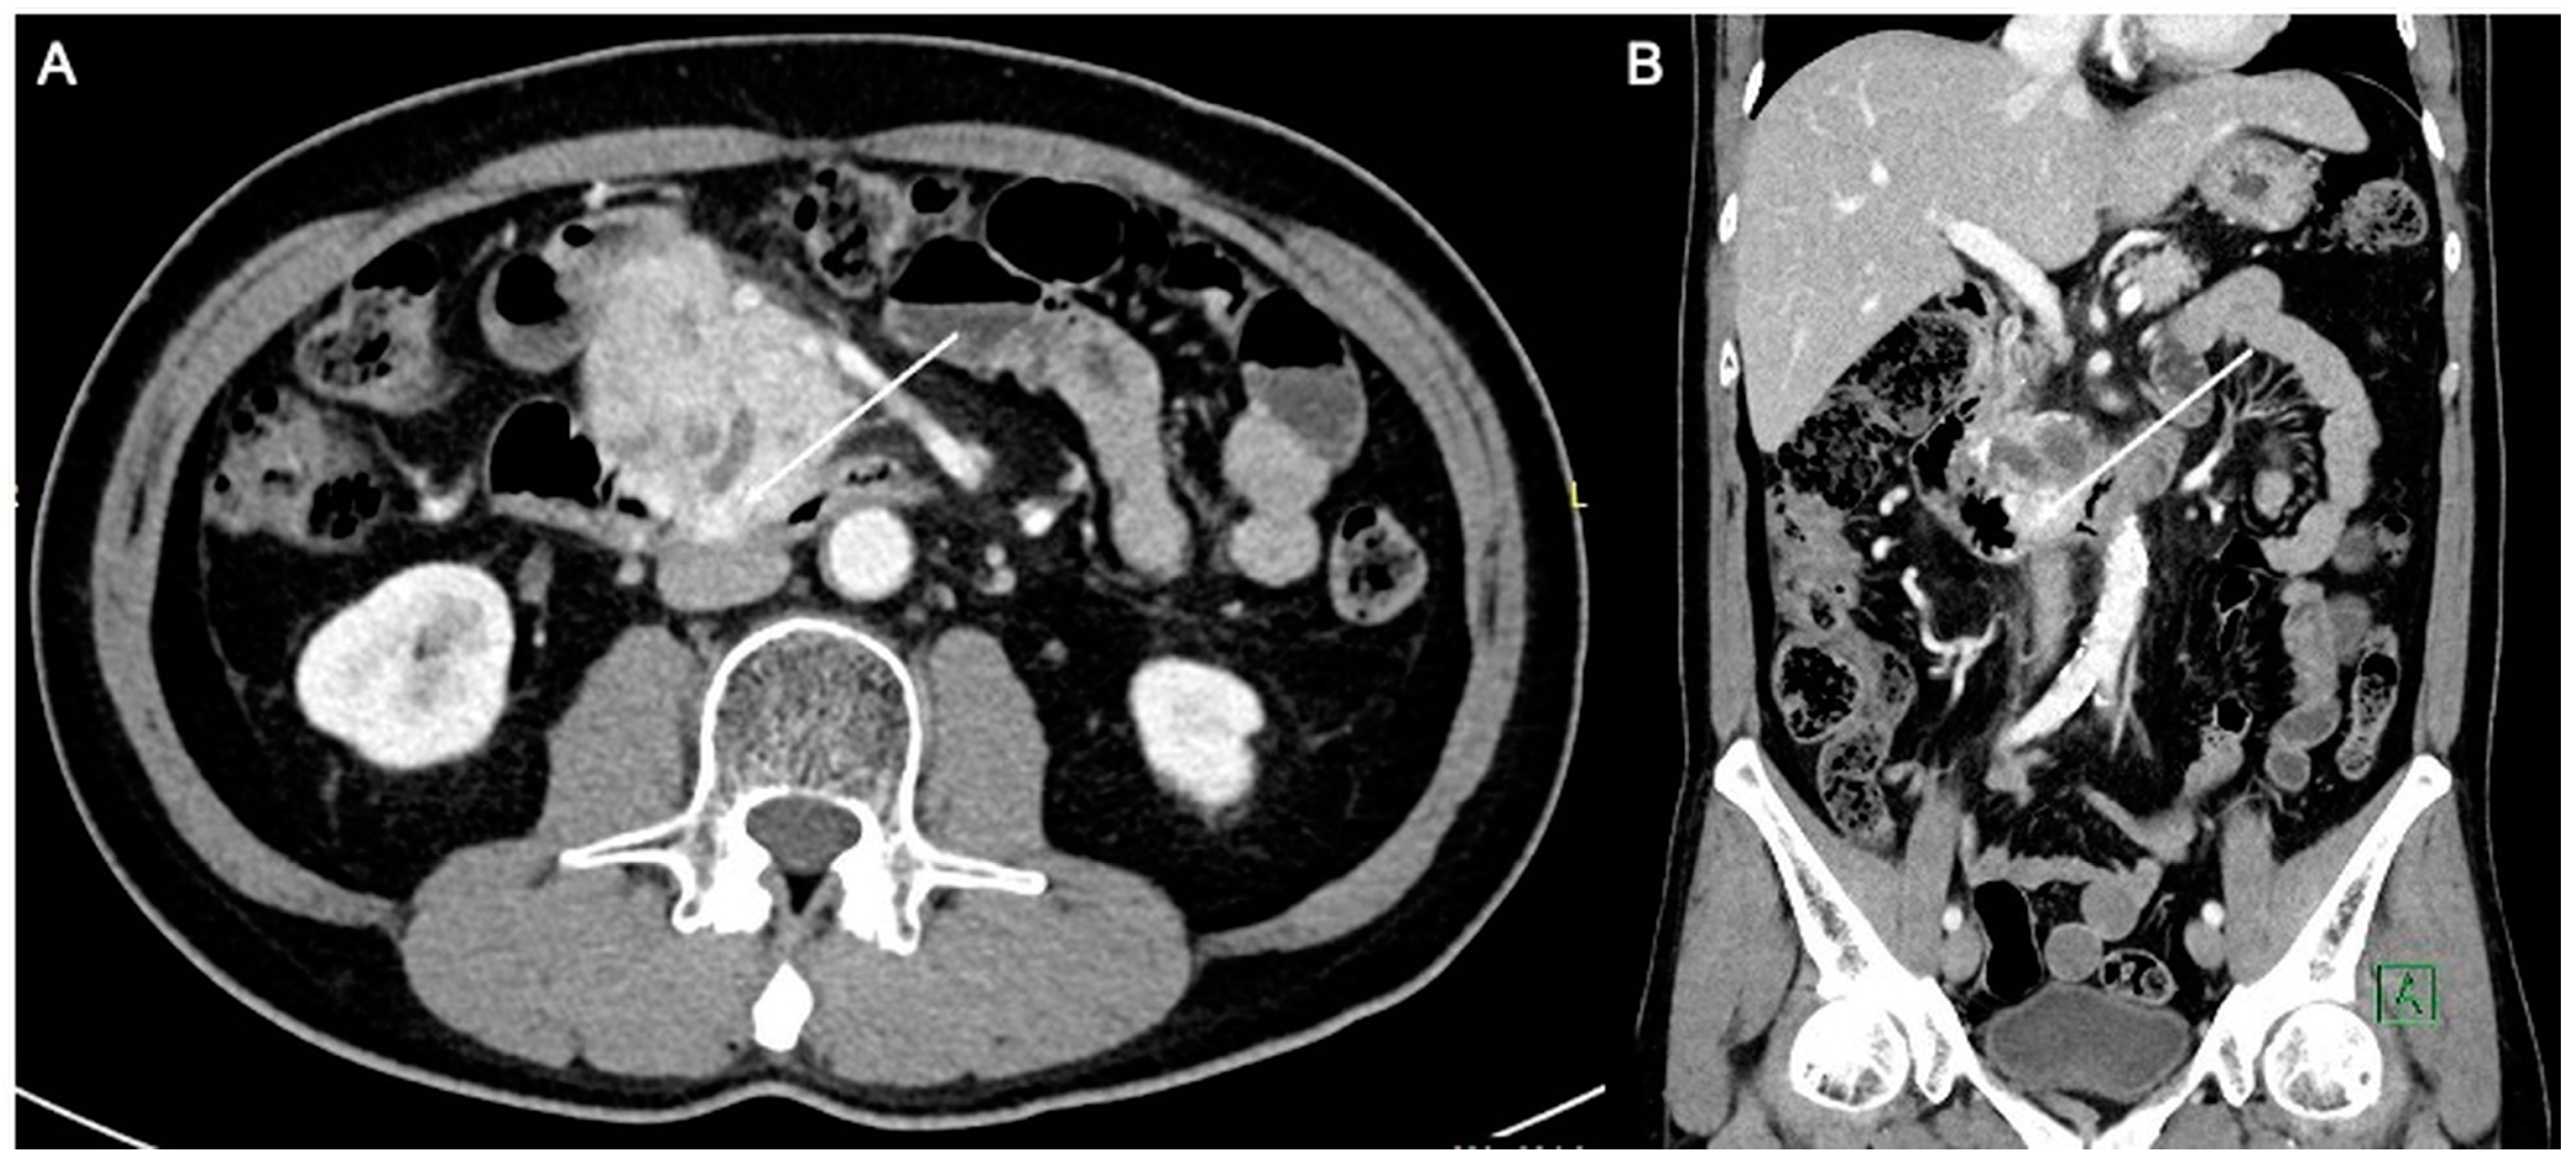

A 59-year-old man with an Eastern Cooperative Oncology Group (ECOG) performance status of 0 presented with LAPC of the uncinate process (biopsy proven pancreatic neuroendocrine carcinoma) with duodenal invasion (Figure 1A,B). The patient underwent a combination of chemotherapy and radiation therapy but was found to have stable disease.

Figure 1.

Axial (A) and coronal (B) computed tomography images of the patient demonstrating a heterogeneously enhancing pancreatic mass measuring approximately 6.3 × 4.4 cm. There is duodenal involvement by the pancreatic mass (arrows).